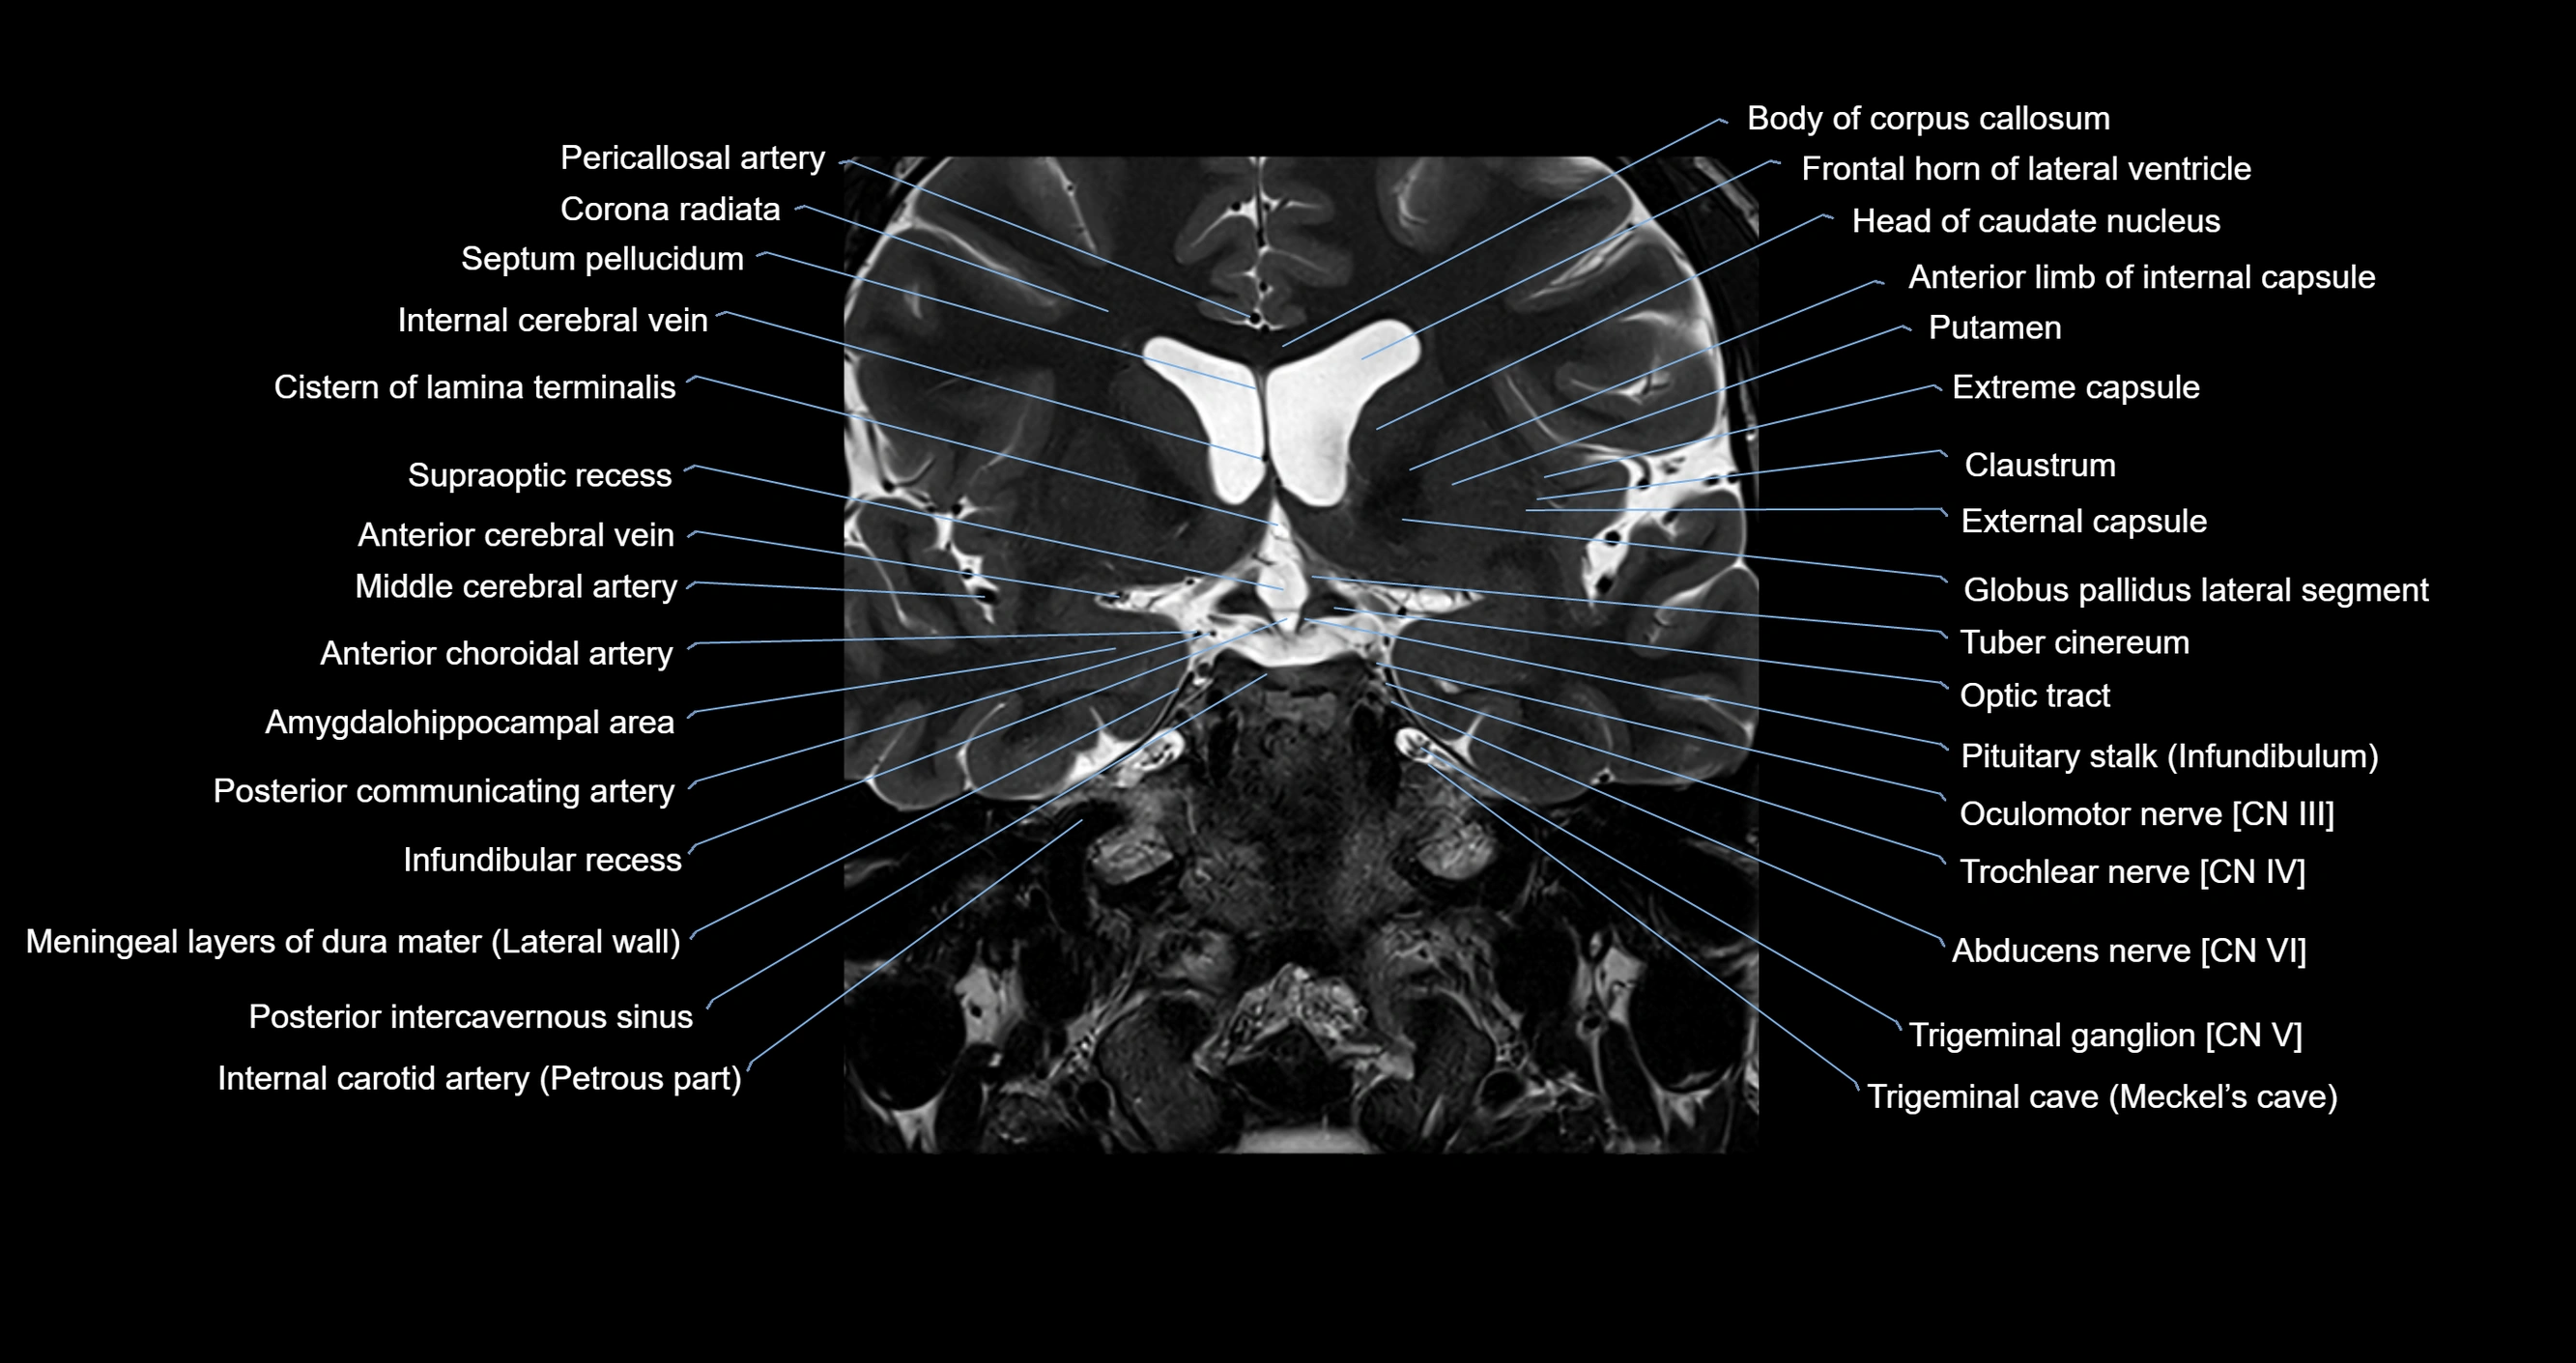

MRI images